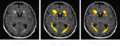

We will continue developing and testing a Slicer module for the white matter lesion segmentation algorithm.

We have developed and tested a Slicer module for WML segmentation. Moreover, we have improved the speed of segmentation stage after training. We will provide the tutorial for this project meeting to present how to use our learning-based white matter lesion segmenation algorithm in Slicer 3. Subtasks implemented include: (1) a skull stripping algorithm working on T1 weighted images; (2) a fuzzy clustering algorithm for tissue segmentation; (3) a parametric model for gain field correction. All of these subtasks are implemented by using ITK. The training step uses AdaBoost and the segmenation step uses a support vector machine.